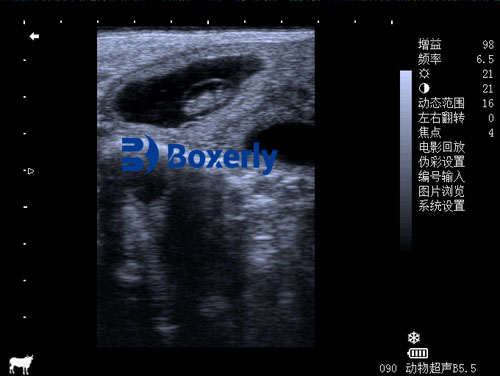

One of the most common uses of ultrasound in cattle farming is pregnancy diagnosis. Ultrasonic devices allow farmers to accurately determine whether a cow is pregnant. This not only confirms pregnancy but also helps in identifying the number of fetuses. In addition, ultrasound technology can provide information on the stage of pregnancy, allowing farmers to better plan breeding schedules and predict calving dates. Early pregnancy detection also plays a critical role in managing the reproductive cycles of cows, ensuring optimal use of breeding resources and improving herd productivity.

44-day pregnant cow ultrasound image